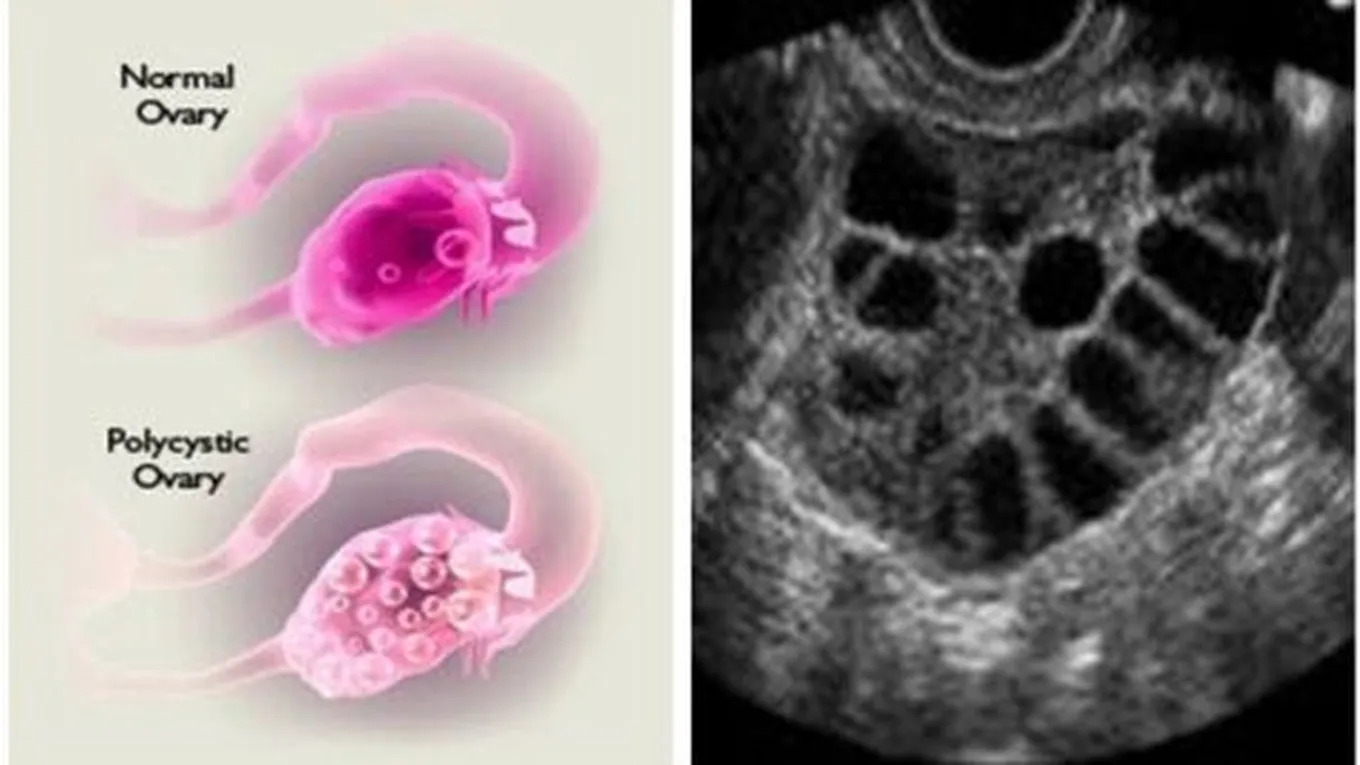

تكيس المبايض هو أحد الامراض التي تصيب النساء وخاصة في مرحلة الشباب ويعتبر سببه الرئيسي الاضطرابات الهرمونية وتعد تفاصيل هذه التغيرات الهرمونية التي من اهمها ارتفاع في مستوى الانسولين والذي يحصل ل50% من حالات النساء .

وهذا المرض شائع جدا حيث يصيب 5% من النساء ومن الاسباب الاخرى لتكيس المبايض هو وجود خلل على مستوى الجينات حيث لوحظ أن الحالة المرضية التي تعاني من تكيس المبايض أحد أفراد عائلتها تعاني من نفس المرض بنسبة 25% ومع تقدم العلم أشارت الدراسات الحالية الى احتماية أن يكون السبب هو خلل في الجين المسؤول عن وظيفة هرمون الانسولين, حيث ان وظيفة هرمون الانسولين هو ان يلتصق بخلايا الجسم ويعمل على انتقال جزيئات الجلوكوز (السكر) من الدم إلى داخل الخلايا بحيث تقوم الخلايا باستخدام الجلوكوز لانتاج الطاقة اللازمة للقيام بالعمليات الأيضية .وعند النساء الذين يعانون من تكيس المبايض تصبح جزيئات الانسولين غير قادرة على ادخال جزيئات الجلوكوز إلى داخل الخلايا .وبالتالي يزداد افراز هرمون الانسولين من البنكرياس حتى يعوض نقص فعالية الانسولين مما يؤدي إلى ارتفاع مستوى الانسولين بالدم والذي يعمل بدوره بتغيرات في المبيضان .